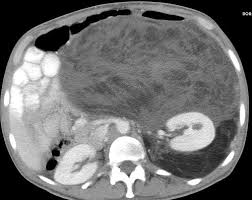

Pin By Hussein Allaw On Ct Radiology Radiology Imaging Gastrointestinal Disorders